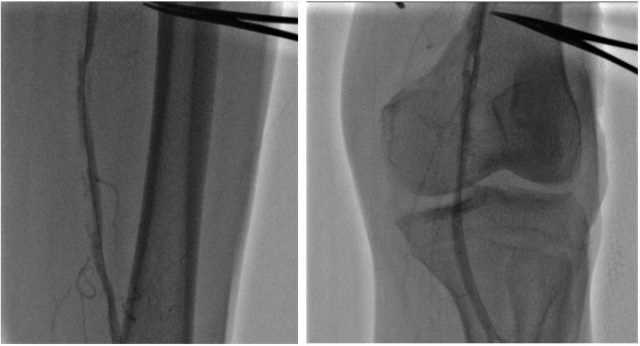

Chụp mạch dưới DSA cho thấy dấu hiệu tắc động mạch chậu trái

Khi thăm khám lâm sàng, bác sĩ ghi nhận động mạch đùi, động mạch khoeo và động mạch dưới gối chân bên trái không bắt được, loét gót chân trái. Kết quả siêu âm Doppler mạch máu chi dưới ghi nhận tắc động mạch chậu bên trái, mất phổ 03 pha động mạch đùi, khoeo chân trái. Bệnh nhân được chụp cắt lớp vi tính mạch máu chi dưới (CTA) để đánh giá cụ thể và chính xác hơn tình trạng bệnh lý của mạch máu.

Kết quả CTA cho thấy tắc động mạch chậu bên trái, tắc 1/3 giữa động mạch đùi bên trái và xơ vữa rải rác các động mạch chi dưới khác. Trước tình trạng tổn thương phức tạp này, các bác sĩ chỉ định can thiệp nội mạch (Endovascular Intervention) để kịp thời tái thông các mạch máu bị tắc gồm động mạch chậu và động mạch đùi nông bên trái.